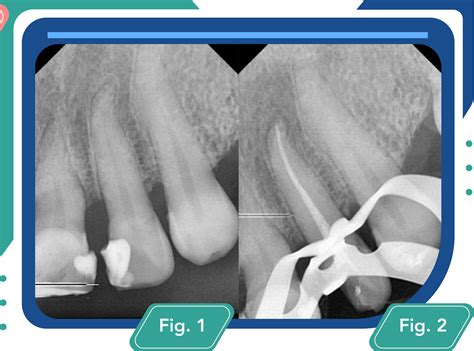

- Diagnóstico y planificación: En esta fase inicial, se realiza una evaluación detallada del diente afectado, incluyendo radiografías. El dentista realiza radiografías para identificar la extensión del daño o la infección.